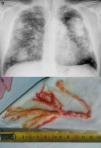

Varón de 49 años con silicosis complicada y antecedentes de tuberculosis pulmonar. Presenta limitación obstructiva al flujo aéreo sin tabaquismo. Consulta por episodios de disnea intensa coincidiendo con expectoración de secreciones espesas sanguinolentas con apariencia de árbol bronquial (fig. 1), que se repiten varios días a la semana. La fibrobroncoscopia no mostró hallazgos relevantes y el estudio anatomopatológico del molde bronquial objetivó material mucoide y fibrinoinflamatorio con abundantes histiocitos.

La bronquitis plástica (BP) es una rara enfermedad pulmonar caracterizada por la formación y expectoración de moldes bronquiales que provocan obstrucción de la luz bronquial1. Se describe como complicación de anomalías linfáticas primarias y en pacientes con enfermedad cardiaca congénita (después de la operación de Fontan), infecciones respiratorias, fibrosis quística, EPOC y aspergilosis broncopulmonar alérgica1. Presentamos el caso de una BP asociada a silicosis. El tratamiento es controvertido, las opciones terapéuticas se basan en casos aislados, destacando la dornasa alfa, macrólidos a baja dosis, suero salino hipertónico y acetilcisteína nebulizados. Existen casos de respuesta a la inhalación de fibrinolíticos y heparina nebulizada1,2. En el caso que presentamos los episodios de expulsión de tapones han disminuido notablemente con prednisona (15mg/día) y heparina sódica nebulizada (5.000UI/12h).